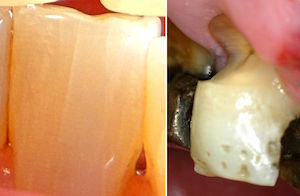

Beachte: Die Fraktur verläuft mesial 2 mm weit durch eine initiale Karies, zentral 6 mm neben einer Amalgamfüllung, und distal 3 mm lang mitten durch eine intakte Kompositfüllung. Diese ist mittig gespalten, aber nirgends vom Zahn abgerissen. Das Zentrum der Amalgamfüllung ist nicht gespalten.

Der Patient ist ein Heavy biter und kam seit Jahren immer wieder mal um Hyperbalancen einzuschleifen. Zudem war dieser +6 der letzte Molar links oben.

Auch auf diesem Röntgenbild ist weder die Hyperbalance noch der kleine Höckerwinkel mit der vertieften Zentrik sichtbar. Die initiale Karies war klinisch nicht sichtbar.